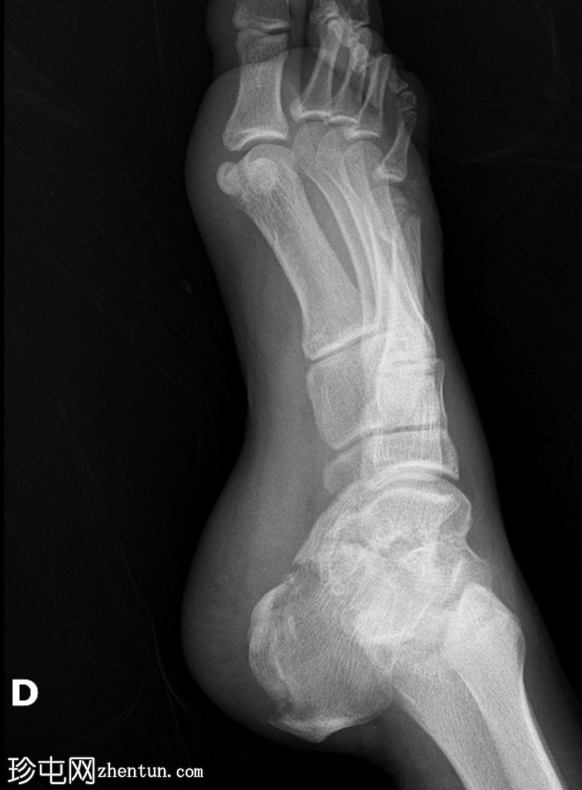

2.png

斜位

第四趾近节指间关节(PIPJ)跖侧脱位。

第五趾近节指骨无移位骨折。

第五跖骨颈骨折伴跖侧移位(背侧成角)。

跟骨关节内骨折。

如果初始影像检查未能清晰显示关节内骨折延伸情况,则应评估Böhler角和Gissane角。本例中,Böhler角减小,Gissane角增大。这两个发现均证实了关节内跟骨骨折。